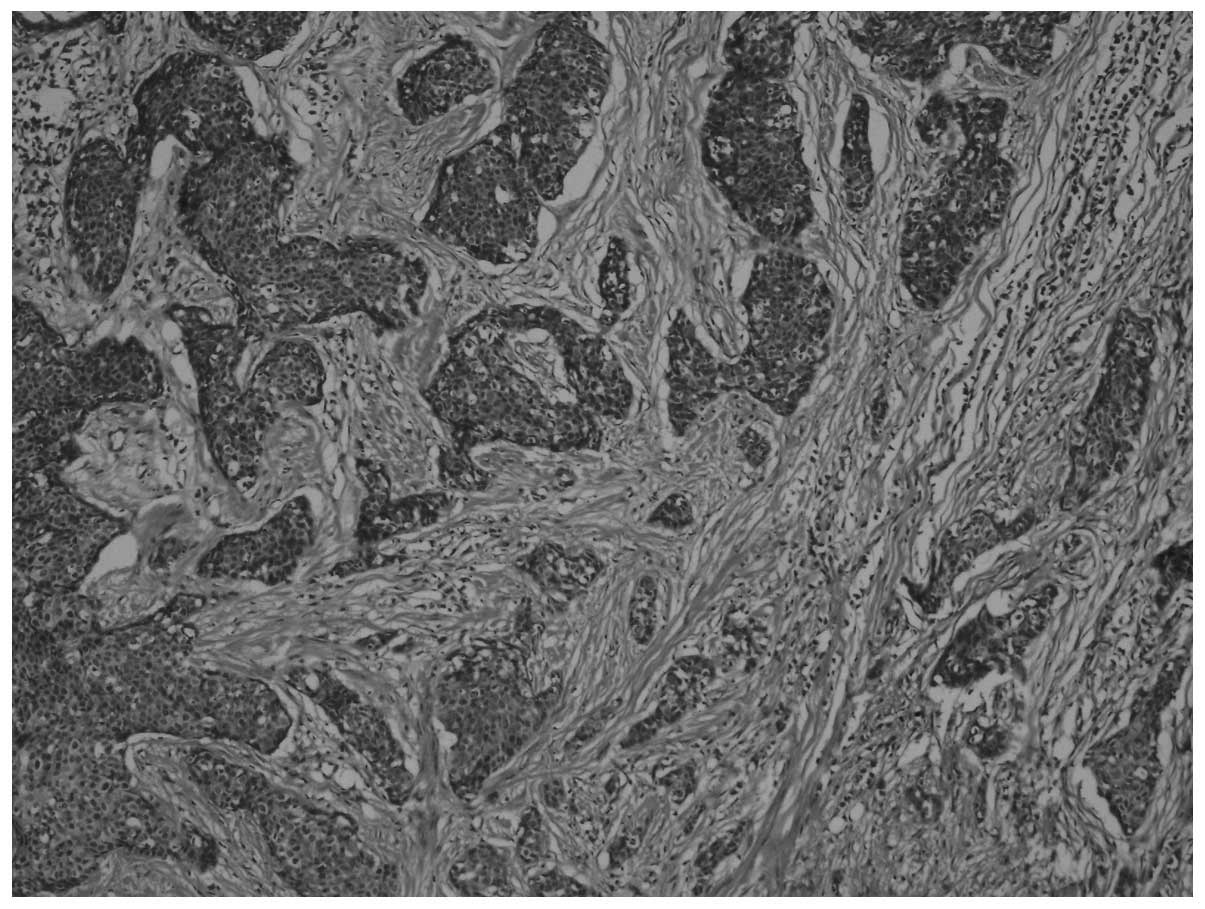

On macroscopic examination, the nephroureterectomy specimen included the left kidney, measuring 18×13×8 mm, a ureteral segment 190 mm in length and a ureteral calculus measuring 25 mm in diameter. The thickness of the renal cortical parenchyma was reduced to 1 mm. Three nodular lesions with irregular margins, brown to dark yellow in color were identified in the kidney, with the largest of the lesions measuring 30 mm in diameter. The total diameter of the nodular lesions was 70 mm. The microscopic examination of the lesions revealed tumor cells with fusiform nuclei and a pink cytoplasm, exhibiting diffuse pleomorphism and areas of necrosis. The mitotic count was 19–20/10 high-power fields. Islands of carcinomatous cells were identified, embedded in a desmoplastic stroma [hematoxylin and eosin (H&E) staining; magnification, x40; Fig. 1]. Sarcomatous areas, composed of pleomorphic fusiform cells with marked atypia were also identified (Fig. 2) (H&E staining, magnification, x40).

Figure 1

Carcinomatous cells embedded in a desmoplastic stroma. Hematoxylin and eosin staining (magnification, x40).